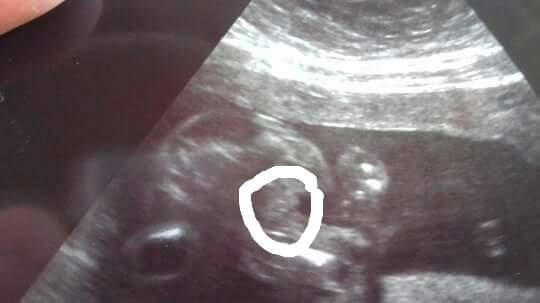

Je to holčička nebo chlapeček? Foto ultrazvuku

@kacenecka_24 Tady hrbolek vidět neni. :( Budes muset vydržet 🙂

Jestli jsem se dobre zorientovala, pripadne mi to na holcicku, nevim. A dr rekla co?

@alhamdulillah pohlavní hrbolek bohužel není dobře vidět 😔

@pampeliska1 tipuji chlapecka..u holcicky by zrejme bylo videt "kavove zrno" .-)